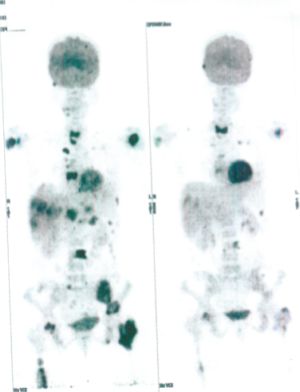

Below are some of the cases, from more than 80 cases we have treated so far with good results. When reading the PET/CT scans, the picture on the left is before treatment, and the picture on the right is after treatment. The intensity of black represents the activity of the cancer, but some black areas are not cancer: brain, heart, radioactive urine in bladder. For the heart, the intensity of black depends on the number of hours of fasting: if more than 10 hours, the heart is not even black, but if fasting is less than 6 hours, it is very black. The intensity of black in the brain can be variable in different scans depending on the brain activity at the time of the scan. The intensity of black in the radioactive urine can also be variable due to the hydration of patients and the time of injection of diuretic.

CASE NO: 5 (BREAST CANCER)

A middle-aged woman with breast cancer that has spread to the anterior chest wall, and numerous chemotherapy could not stop the spread of cancer. After a few treatment, almost all the cancer went into remission. About 6 months later, she is still in remission.

CASE NO: 6 (BREAST CANCER)

A middle-aged women treated for breast cancer now presents with massive liver metastases and a few bone metastases. She refused conventional chemotherapy and came to see us. After just 2 treatment, most of the cancer went into remission and those remaining are less active. Treatment will continue until complete remission.

CASE NO: 7 (BREAST CANCER)

A middle-aged woman treated for breast cancer now presents with bone and liver metastases. After a few treatment, most of the cancer went into remission, and the remaining ones are less active.

CASE NO: 8 (BREAST CANCER)

A middle-aged women treated for breast cancer now present with bone and right lung metastases. After just 2 treatment, almost all the cancer went into remission, but treatment is continuing to prevent recurrence.